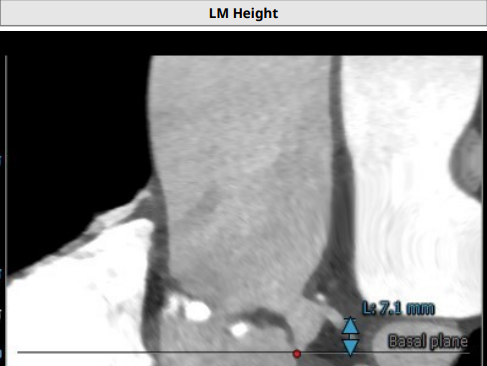

左冠高度7.1mm, 右冠高度13.2mm.

患者为TYPE1型二叶瓣,重度钙化,左右可见钙化脊,左冠高度低,可能存在较高的冠脉风险,该患者对于瓣膜释放位置要求较高,容错空间很小,法式窦结构可,需要在术中球囊扩张时着重观察冠脉即刻情况且做出相应判断。左室大小可,升主动脉未见明显扩张,心脏角度43°。